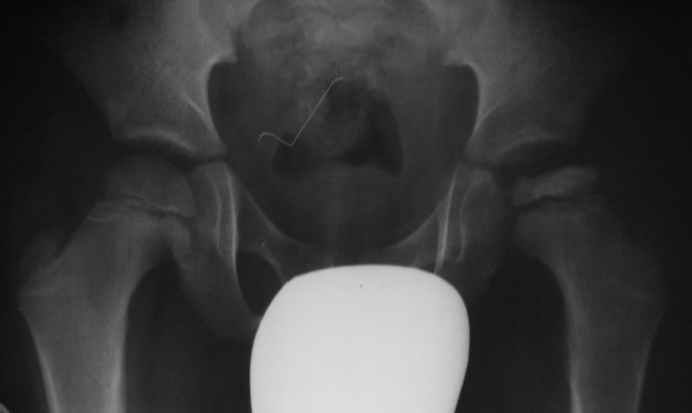

Сын близких моих приятелей три месяца назад стал прихрамывать и жаловаться, что "устает ножка". Лечение у парамедиков без инструментального обследования. Мальчику 7 лет. Направил на снимок.

По моему мнению это болезнь Пертеса. Вопрос, прежде всего к детским ортопедам, относительно необходимого еще обследования и дальнейшего лечения.

Юрий Алексеевич, по рентгенограмме болезнь Пертеса,2-3 стадия по Рейнбергу. Для более полной оценки патологического процесса целесообразно сделать сравнительные рг.

в положении по Лауэнштейну. При выборе тактики лечения придерживаемся четырёхступенчатой схемы Catteral. Тип 1,2 консервативно, 3,4 оперативно.

Основной тип оперций - профилактический, прежде всего это варизирующая межвертельная остеотомия, позволяющая сохранить конгруэнтные взаимоотношения в тазобедренном суставе за счёт выведения наиболее поражённого участка эпифиза г.б. из под нагрузки .

В приведённой ситуации, судя по рг. это будет 3 тип по Catteral, субтотальное поражение эпифиза, т.е показание к операции.

На ренгенограмме тазобедренного сустава: слева увеличена медиальная щель, что означает подвывих сустава, срочным устранением подвывиха можно было бы предупредить осложнения, встречающиеся на головке бедра.